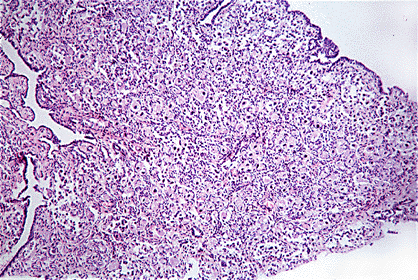

El epitelio germinal (simple, células cuboides) cubre la capa albugínea de tejido conjuntivo. La corteza contiene abundantes oocitos